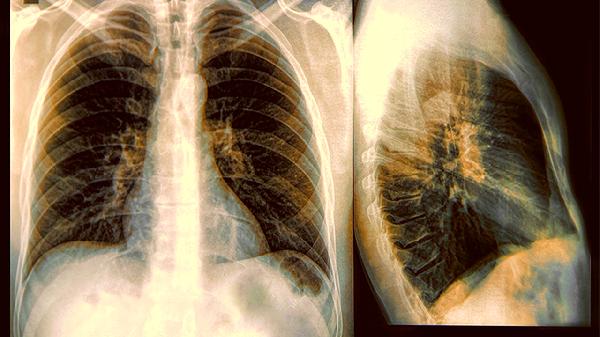

病毒或支原体感染可破坏气道纤毛功能,使黏液清除能力下降,痰液黏稠度增加。急性期需进行病原学检查,细菌性感染可选用阿奇霉素等大环内酯类药物,病毒感染则以对症支持为主。

日常需保持每日2000毫升温水摄入稀释痰液,练习腹式呼吸促进排痰,饮食避免牛奶等易生痰食物。症状持续加重或痰液转黄绿色时需及时进行肺功能检查,排除合并细菌感染可能。长期管理建议记录痰量变化日记,定期复查气道炎症指标调整用药方案。